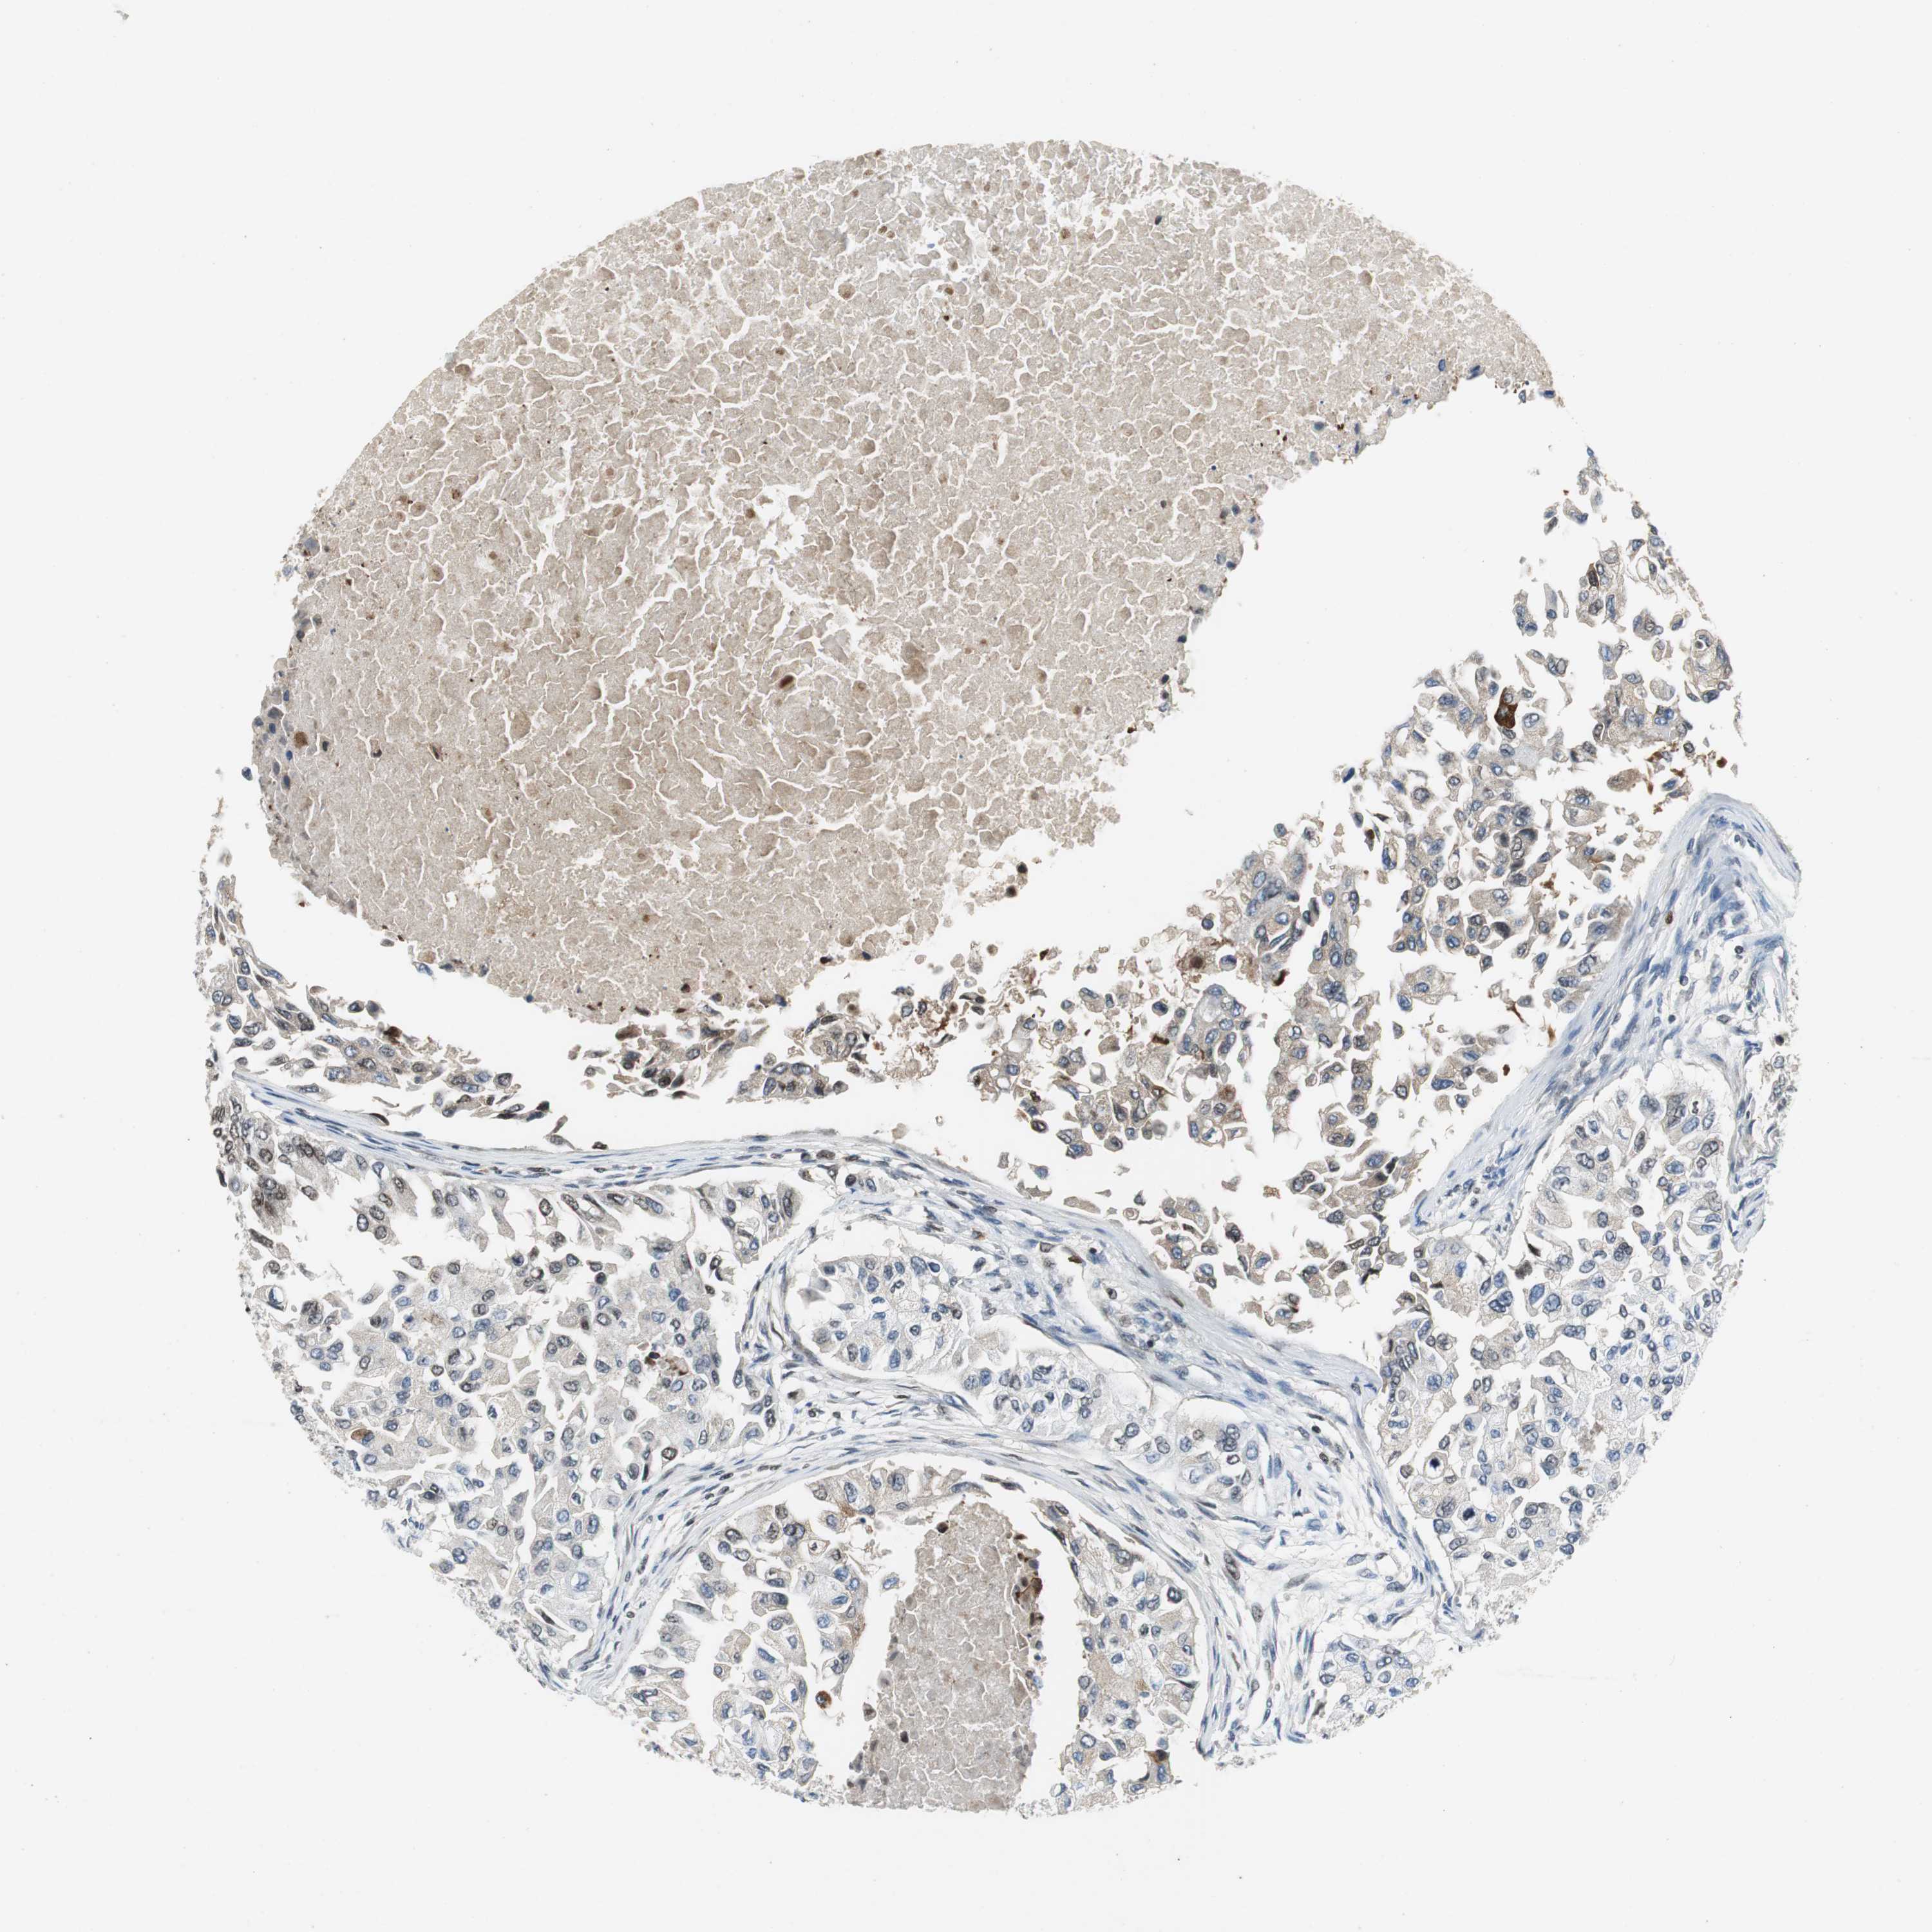

BRCA TCGA BRCA VALIDATION PROTEIN EXPRESSION

ANTIBODIES

AND

VALIDATION